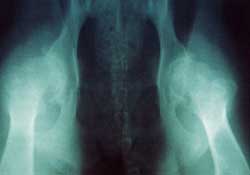

| Hip dysplasia (HD) is a term which encompasses

a number of specfic developmental & other abnormalities

involving the hip joint. Developmental changes come first and

being related mainly to growth are known as primary changes.

Others come later; these are related to wear and tear from usage

and are termed secondary changes. The end result is that one

or pair of joints becomes mechanically unsound and therefore

does not function properly. An unsound joint is usually a painful

one and lameness will result. In extreme cases the dog may find

movement very difficult and much suffering will be involved.

It was in the light of these findings that the British Verterinary

Association (BVA) and the Kennel Club (KC) developed a scheme

over 30 years ago to assess the degree of hip malformation

of dogs through radiography. Over this time almost 100,000

radiogarphs (X-rays) have been examined to providde a standardised

opinion on HD status, principally for the use of breeders.

Currently 97 breeds are surveyed by the scheme in the UK.